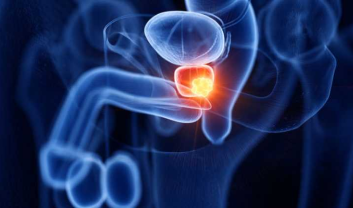

Prostate cancer, a form of cancer that develops in the prostate, a small gland producing seminal fluid, poses a significant threat...